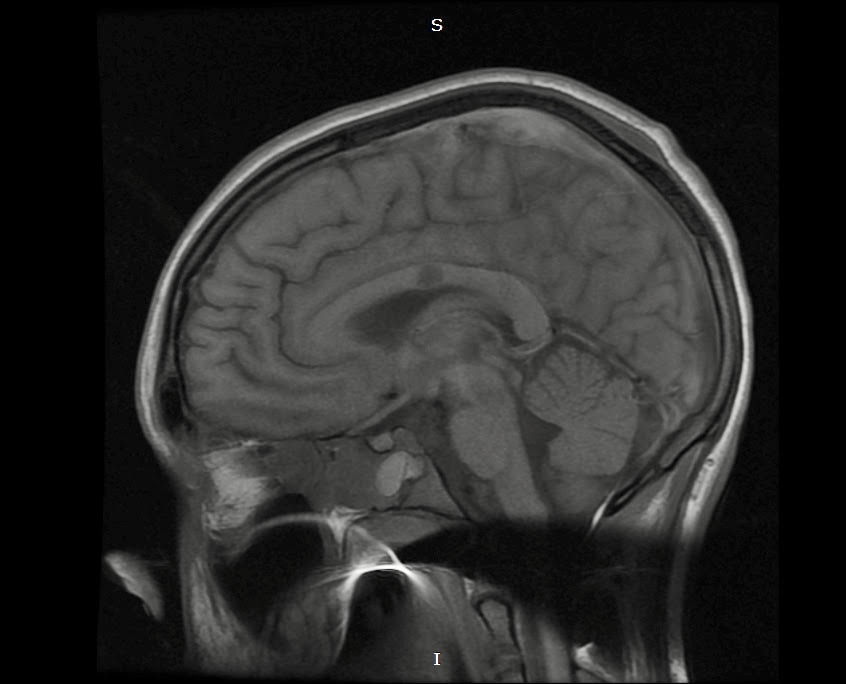

Here I have some CT and MRI images taken soon after my injury. The blurred parts of the MRI image towards the center show evidence of shearing. In addition, the bright white portions of the CT images represent accumulations of blood, known as hemorrhages. These also contributed to the extent of my injury. Had the emergency staff not implanted what is known as an intracranial pressure cup (ICP) to relieve the pressure from the excess fluid within my cranial cavity, my brain would have been displaced and squished down by the fluid, and the extent of my injury would have been much worse, potentially even fatal.